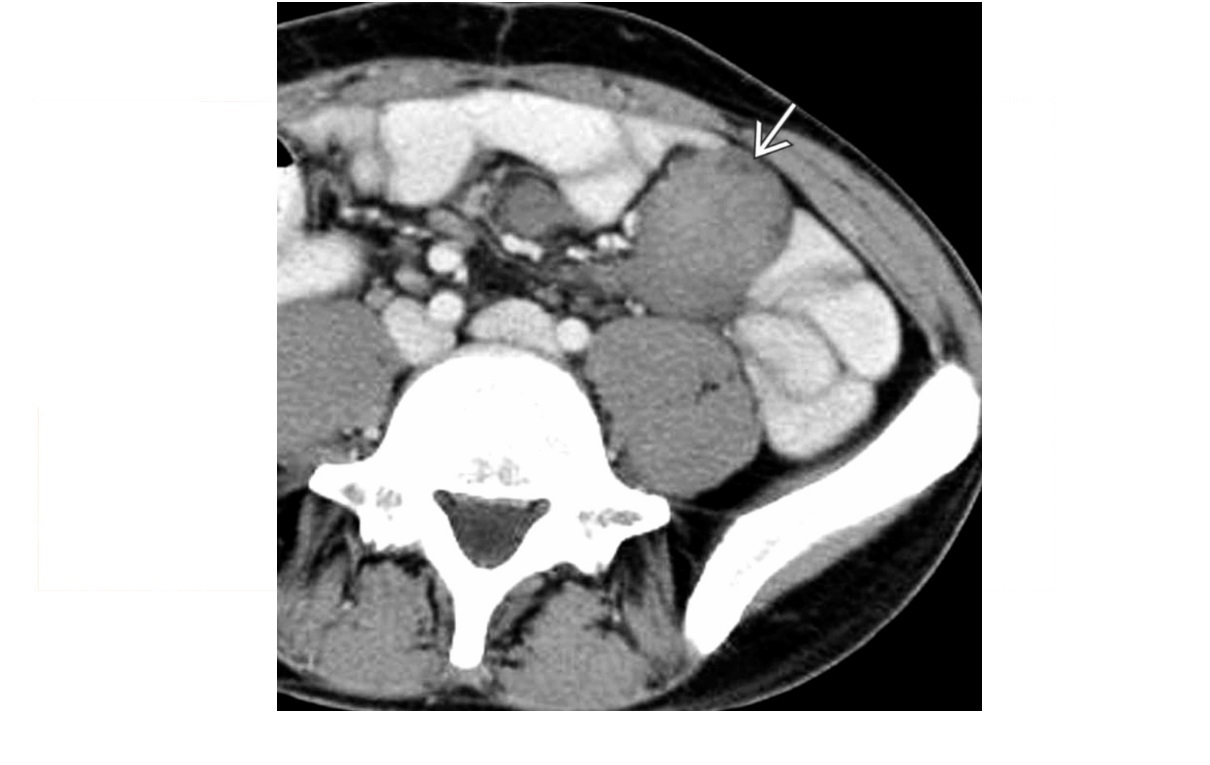

Carcinoid

spiculated mesenteric mass with calcification/ desmoplastic reaction

Tethering of SB loops

90% arise in terminal ileum/appendix

Hyper-vascular liver mets - Carcinoid syndrome

111I- Octreotide scans (1st - highest sensitivity)

or 123I-MIBG (for 10% dont take up octreotide)

for Dx and staging

Big centres use gallium PET

Assocaited with MEN 1 or MEN 2a

DDX

Sclerosing mesenteritis/ mesenteric pannicultuis

- FAT HALO sign - Mass envelop vessels, but preservation of fat around vessels

- usually jejunal small bowel mesentery

Gastrointestinal Stromal Tumor (GIST)

- Hypervascular tumor, not associated with desmoplastic effect on mesentery

Small Bowel Carcinoma

- More common in duodenum or jejunum than in ileum

- Causes luminal obstruction

- Mass and metastases are hypovascular